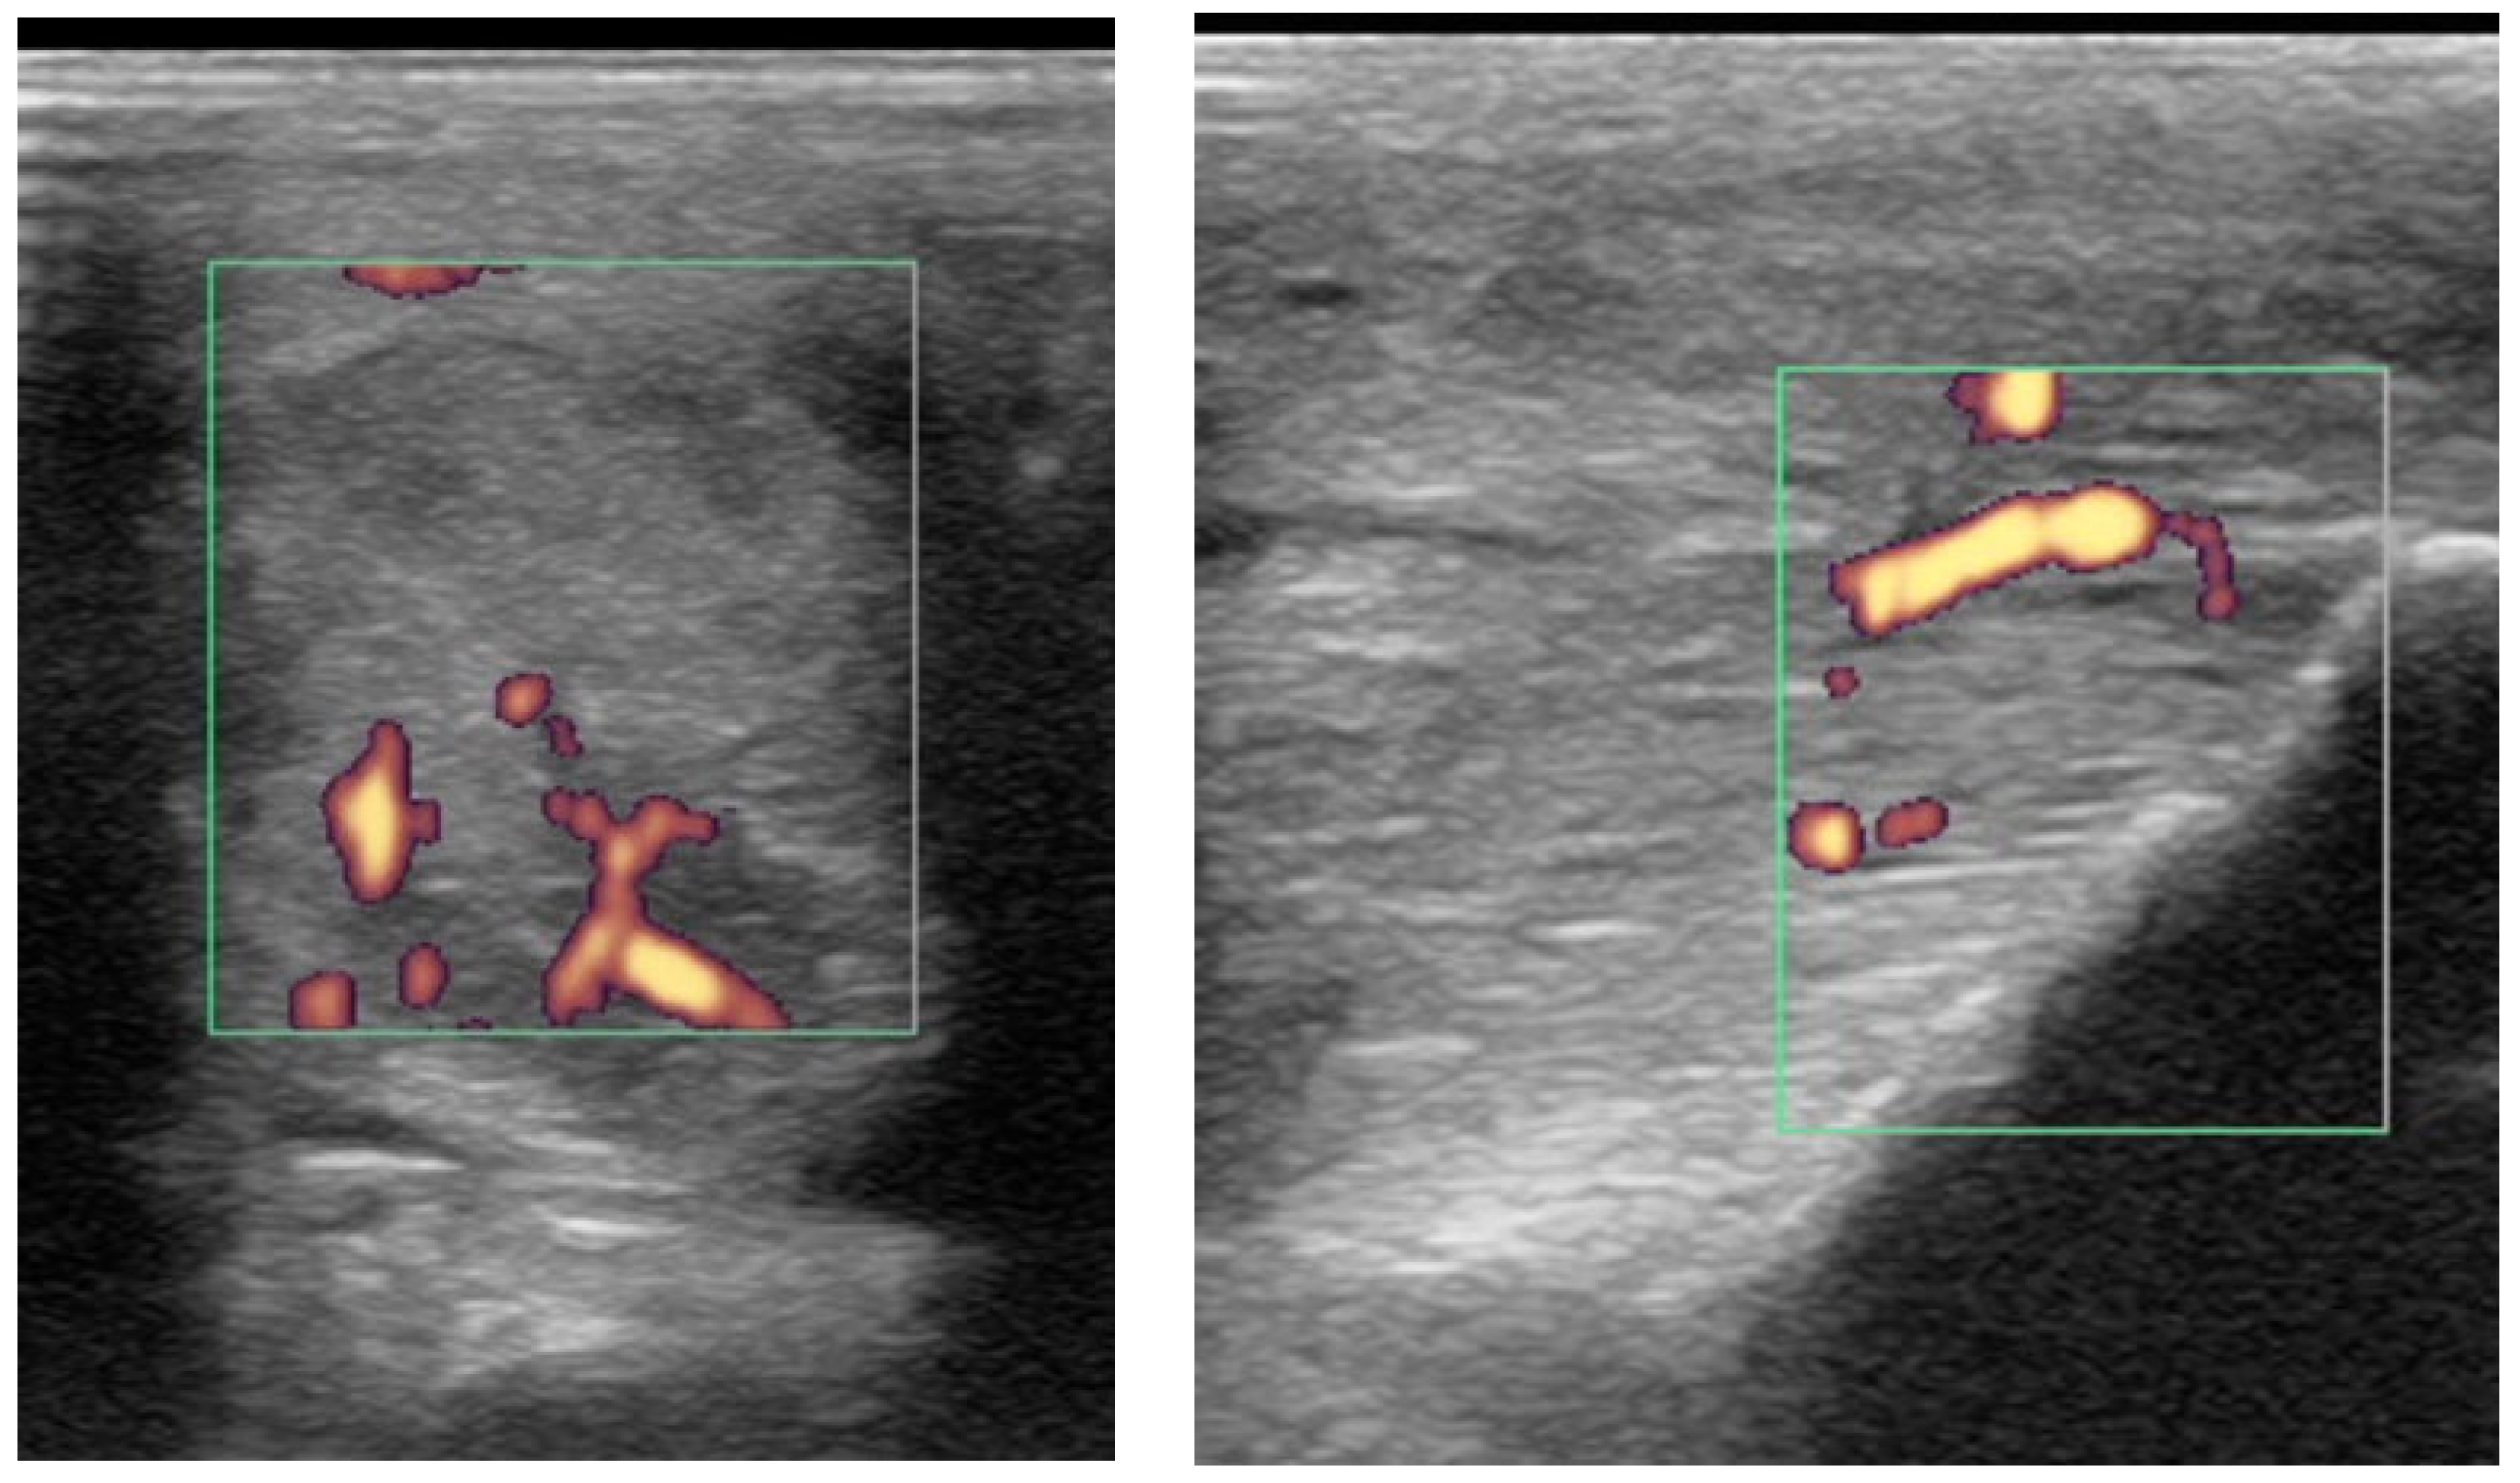

2.3.2. Power Doppler Examination

3.2. Diagnostic Ultrasonography

3.3. Power Doppler Examination

4.2. Power Doppler

4.3. Monitoring: The Use of Power Doppler in Non-Healed Cases; Uncontrolled Inflammatory Response